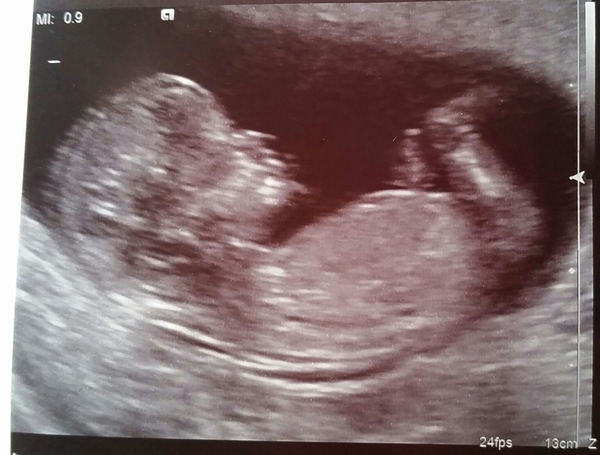

Hi everyone, sorry I've been so busy I haven't RTFT for a long time, but I know everyone likes a scan photo, so here's mine. Very seamless process, but make sure you tuck the tissue in your trousers properly or you get very gloopy jeans from the gel (oops!). Hope everyone is well and good luck for those with scans soon!

12+0, now due 4th July

Lovely pic foo! X